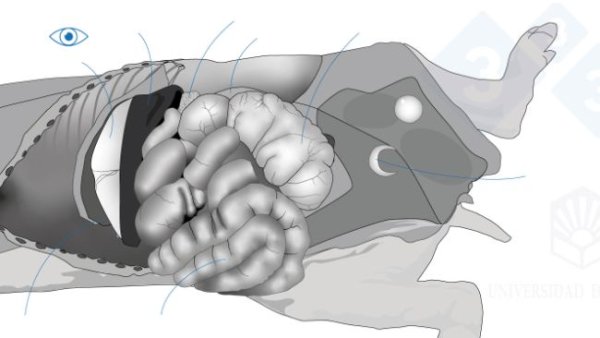

Mientras que en las dos primeras entregas hemos abordado la necropsia en decúbito lateral, en esta tercera entrega explicaremos como hacer la necropsia en decúbito supino.

En la cuarta entrega del manual abordamos el examen de los órganos de la cavidad torácica.

En la quinta entrega del manual abordamos el examen de los órganos de la cavidad abdominal.